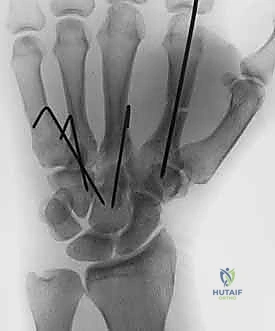

- صور الأشعة السينية المتخصصة (X-Rays): لا يكتفي الدكتور بالصور التقليدية، بل يطلب وضعيات تصوير خاصة (مثل الوضعية المائلة Oblique View بـ 30 درجة) التي تظهر قاعدة المشط بوضوح وتكشف الخلع الخفي.

* أسلاك كيرشنر (K-wires): أسلاك معدنية دقيقة يتم إدخالها عبر الجلد لتثبيت عظم المشط بعظام الرسغ المجاورة. تُزال هذه الأسلاك في العيادة بعد 4 إلى 6 أسابيع.